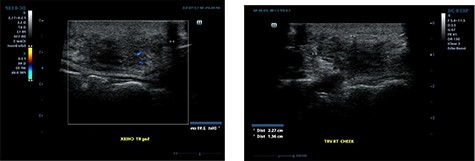

Ultrasound examination revealed a heterogenous lesion measuring 2.9 × 2.3 × 1.4 cm, with associated non-specific ipsilateral Level II cervical lymph nodes (Fig. 1). Haematological test results showed a leukocyte count of 8.47 × 109/l with an eosinophil rate of 17.4% (normal range is 1–5%) and normal renal function.

Ultrasound examination demonstrating a heterogenous lesion measuring 2.9 × 2.3 × 1.4 cm mass.